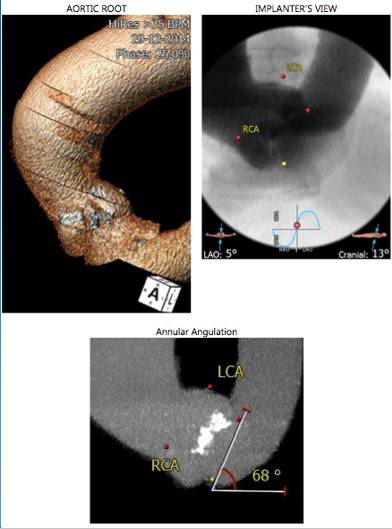

主动脉及瓣膜CTA

◆Annulus (mm)

◆Min 24.3mm

◆Max 28.3mm

◆Mean 26.3mm

◆Perimeter 82.5mm

THV 29mm

◆2015年1月17日行TAVI术。

◆植入29mm CoreValve人工支架瓣膜一枚。

术后症状明显缓解,近一年未因心衰住院;

一年期复查心超,未见主动脉瓣狭窄和关闭不全。